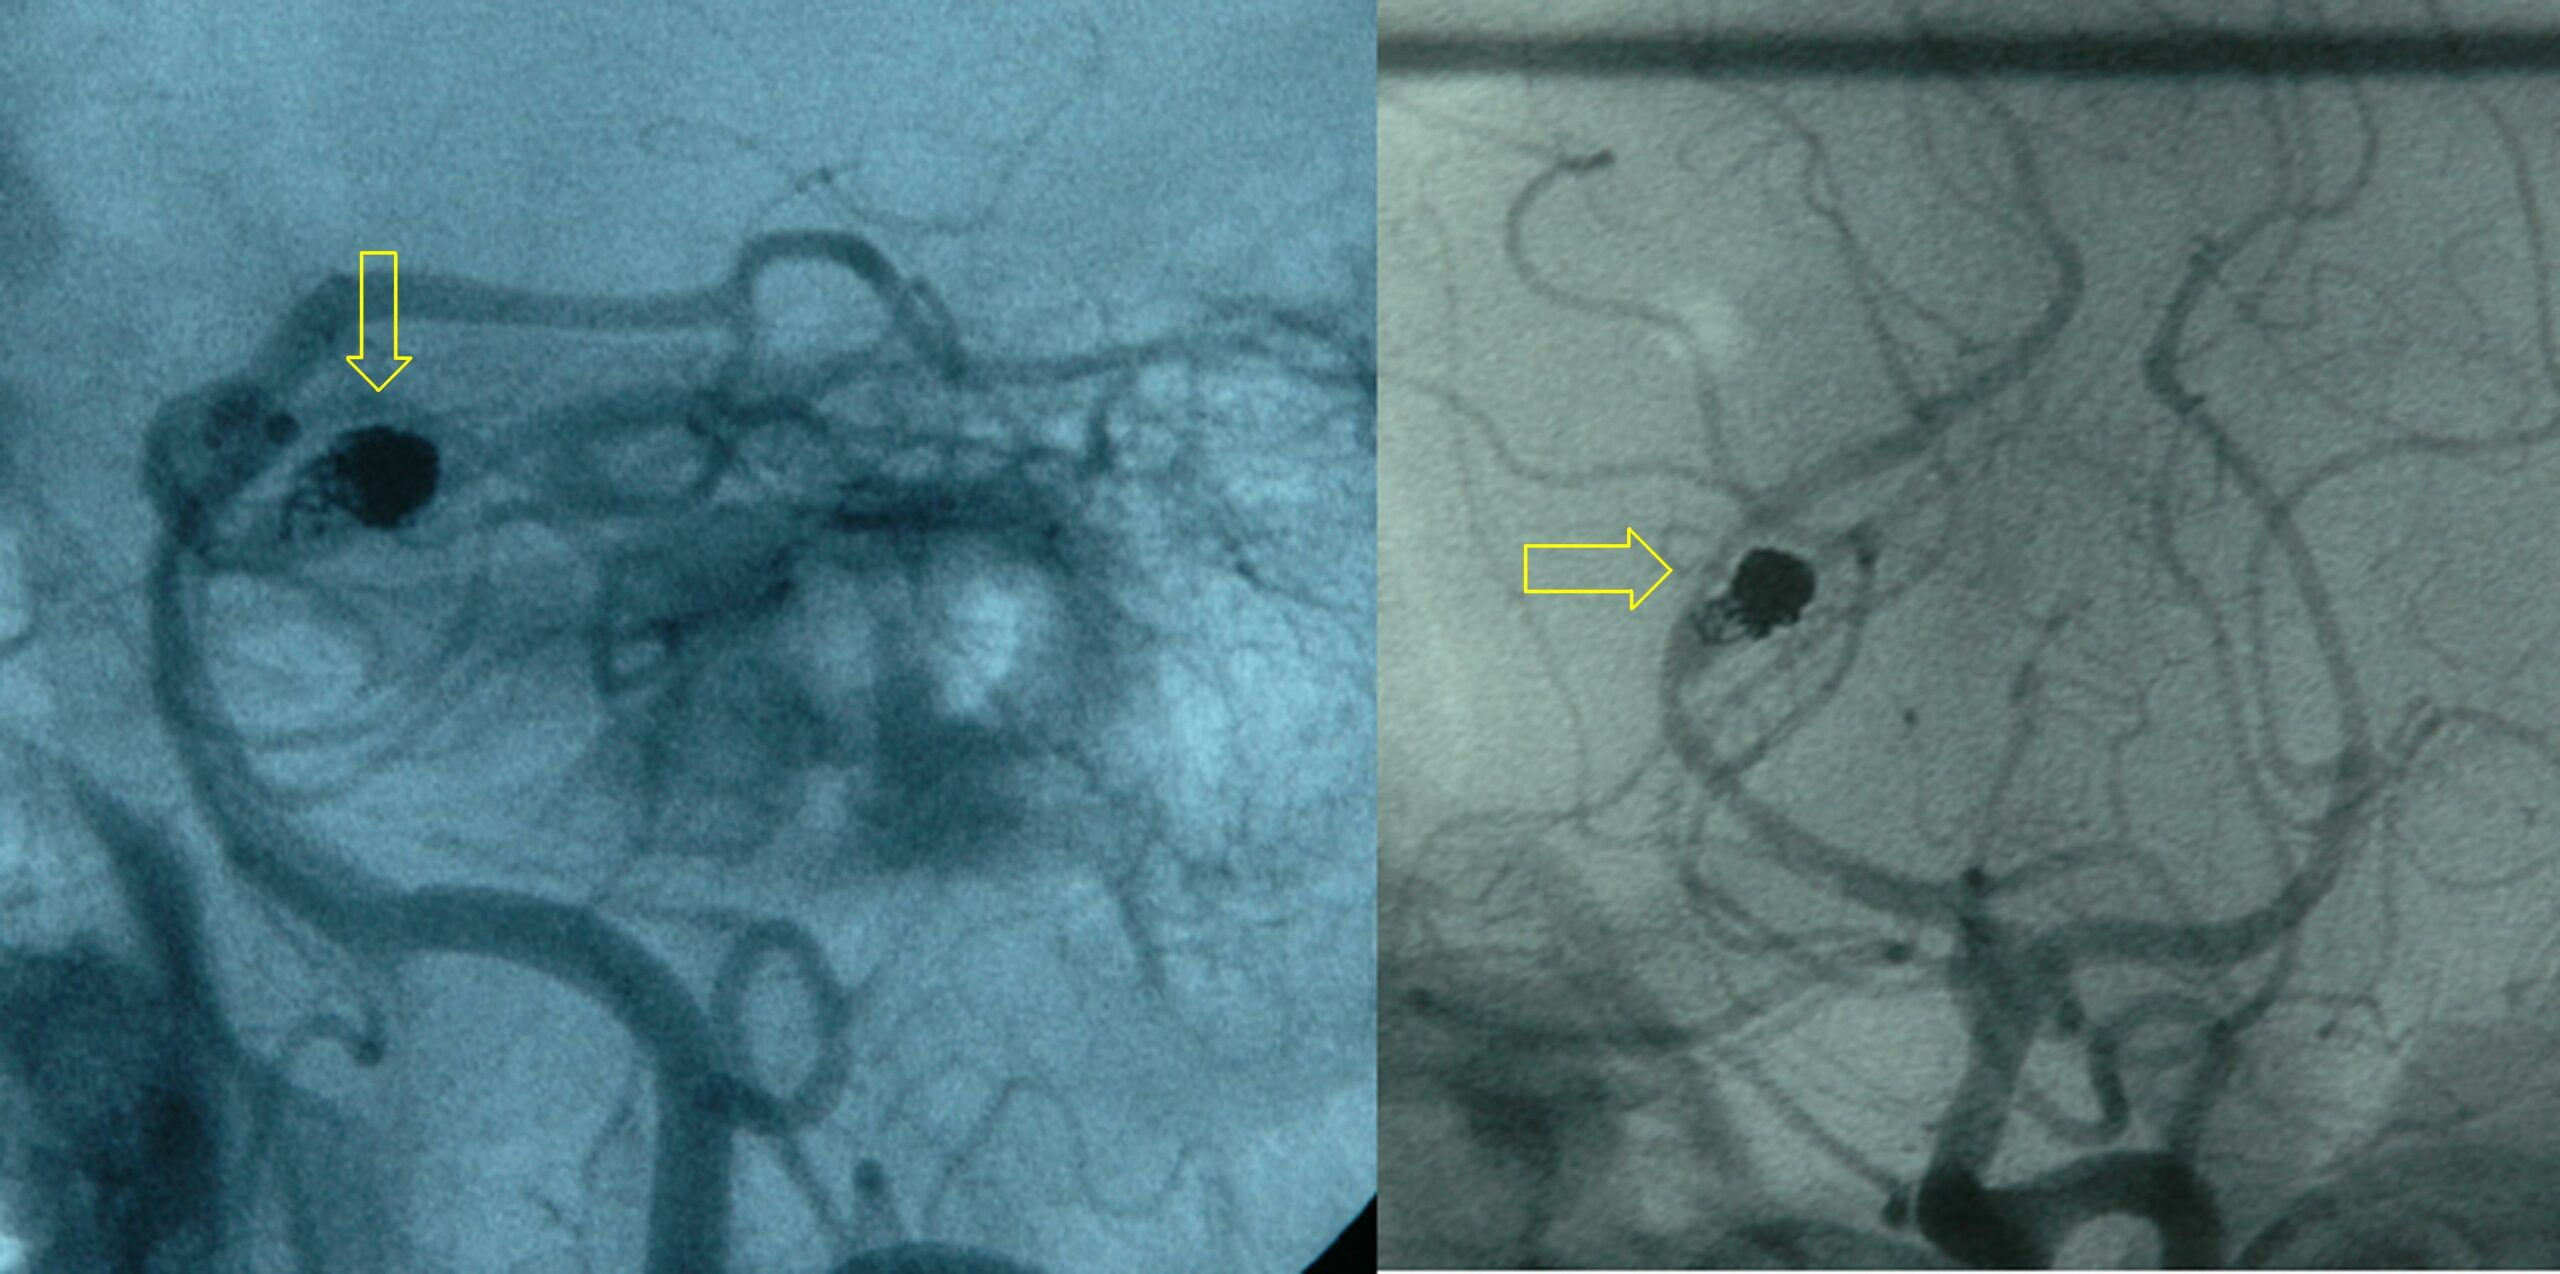

Coiled PCA residual aneurysm arteriogram.